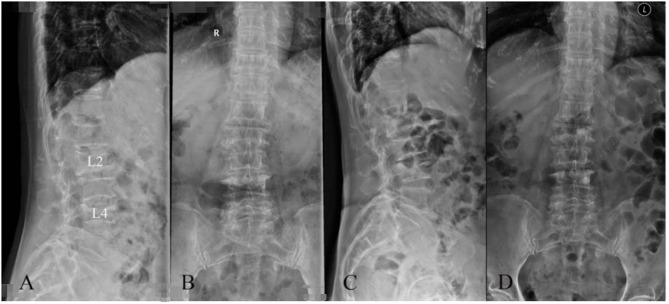

Case report: We designed a prospective cohort study to evaluate the outcomes following of percutaneous vertebroplasty using GeneX in patients with osteoporotic vertebral compression fractures. Vertebroplasty was performed at seven vertebrae in the first seven patients. Overall, there were four leaks in four (57%) of the seven patients. Asymptomatic leak of the GeneX material into the intradiscal and paravertebral structures at the treated vertebral level was observed in three patients (43%). However, the material leaked into the intradural and epidural space in the seventh patient (14%), causing severe neurological deficits. Primary diagnosis was bone cement implantation syndrome. The patient's neurological status improved gradually during the month after surgery. She was able to resume her activities of daily living and had regained her urinary function by 3 months after surgery.